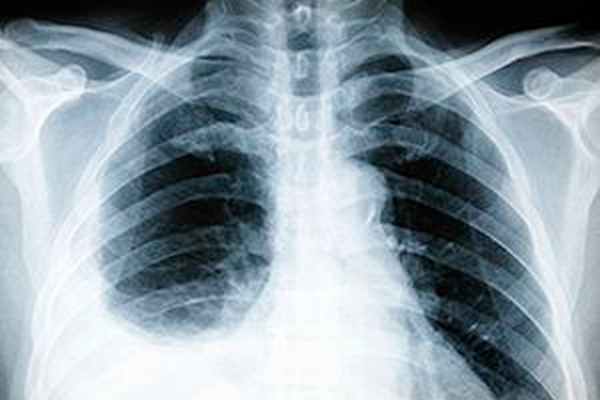

Диагностика плеврита

Диагностика плеврита начинается с осмотра врача. У пациента даже визуально отмечаются асимметрия грудной клетки. Пораженная сторона отстает пи дыхании. Дыхание становится очень слабым, почти не прослушиваемым.

Чтобы диагностировать плеврит у взрослых, дополнительно назначают следующие обследования:

Особенности диагностики

Лечение плеврита у взрослых начинается с комплексной диагностики, проводимой в несколько этапов:

Инструментальные методы. К ним относят рентгенографию, компьютерную томографию, по показаниям плевральную пункцию с исследованием полученного материала, УЗИ плевральных полостей и сердца, торакоскопия и др.